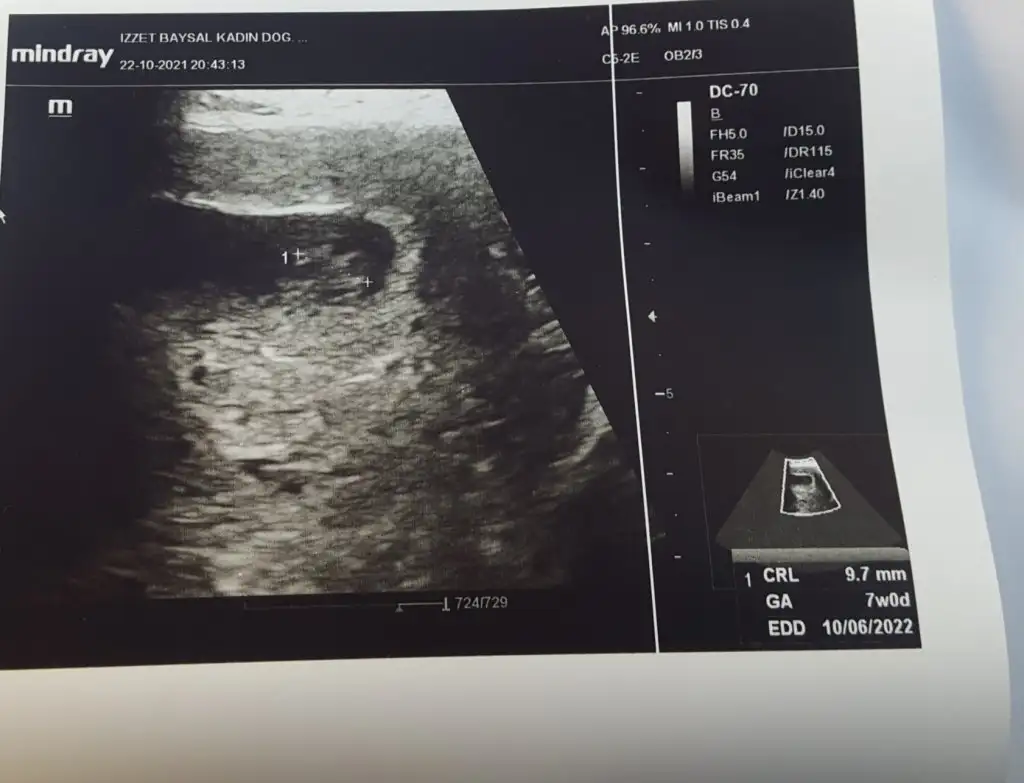

Kesede ilk gördüğünüz usg görüntüsü varsa 6.haftalardan falan bi gönder bakalım. 😉

Tatlı yedim gitmeden çocuğum resmen halay çekiyordu🎈🙏😍😘😘 bunu buldum

Selam kızlar bugün gittim kontrole bebişimi detaylı şekilde gördük çok şükür ablası geldi diye show yaptı deli baklam kıpır kıpırdı çok şükür elhamdülillah rabbim sağlık versin tüm evlatlarımıza progestana devam tabii :KK200::dua:cinsiyet tahmini varmıı:nazar::anneadayı::anne:

Oyy maşallah çok şükür canım ne güzel gözüküyor demi kıpır kıpır oynaması 🥰bende çok şaşırmıştım 9 haftada görünce